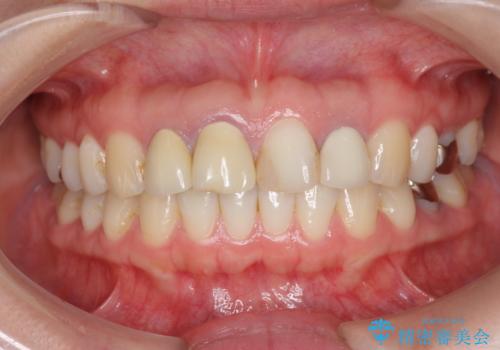

前歯の見た目を改善したい

- 前歯を天然の歯のようにきれいにやりかえたいと希望され来院されました。

根尖病変の存在が判明したため、感染根管治療後にオールセラミックジルコニアクラウンを製作します。

審美的なジルコニアクラウンを装着し、審美性が回復されたと満足いただくことができました。